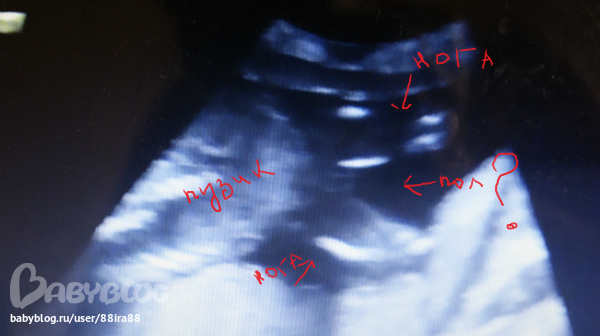

может кто понимает чтото в узи если не трудно посмотрите

первые 7 фото это 19+4 недели

и мне сказали что девочка на 2х узи в 19+4 недель и в 25 недель а вот в 31 сказали кажется мальчик но не точно